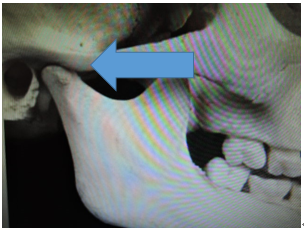

この写真の顎関節は小学校5,6年の形です。

顎関節の前方部の隆起が毎月、毎月成長していきます。

この為に、下顎骨を前方に適応させることが難しくなり上顎前突(出っ歯)の症状が突然目立ってきます。

この為に下顎骨を前方に適応させることが難しくなり、上顎前突(出っ歯)の症状が突然目立ってきます。